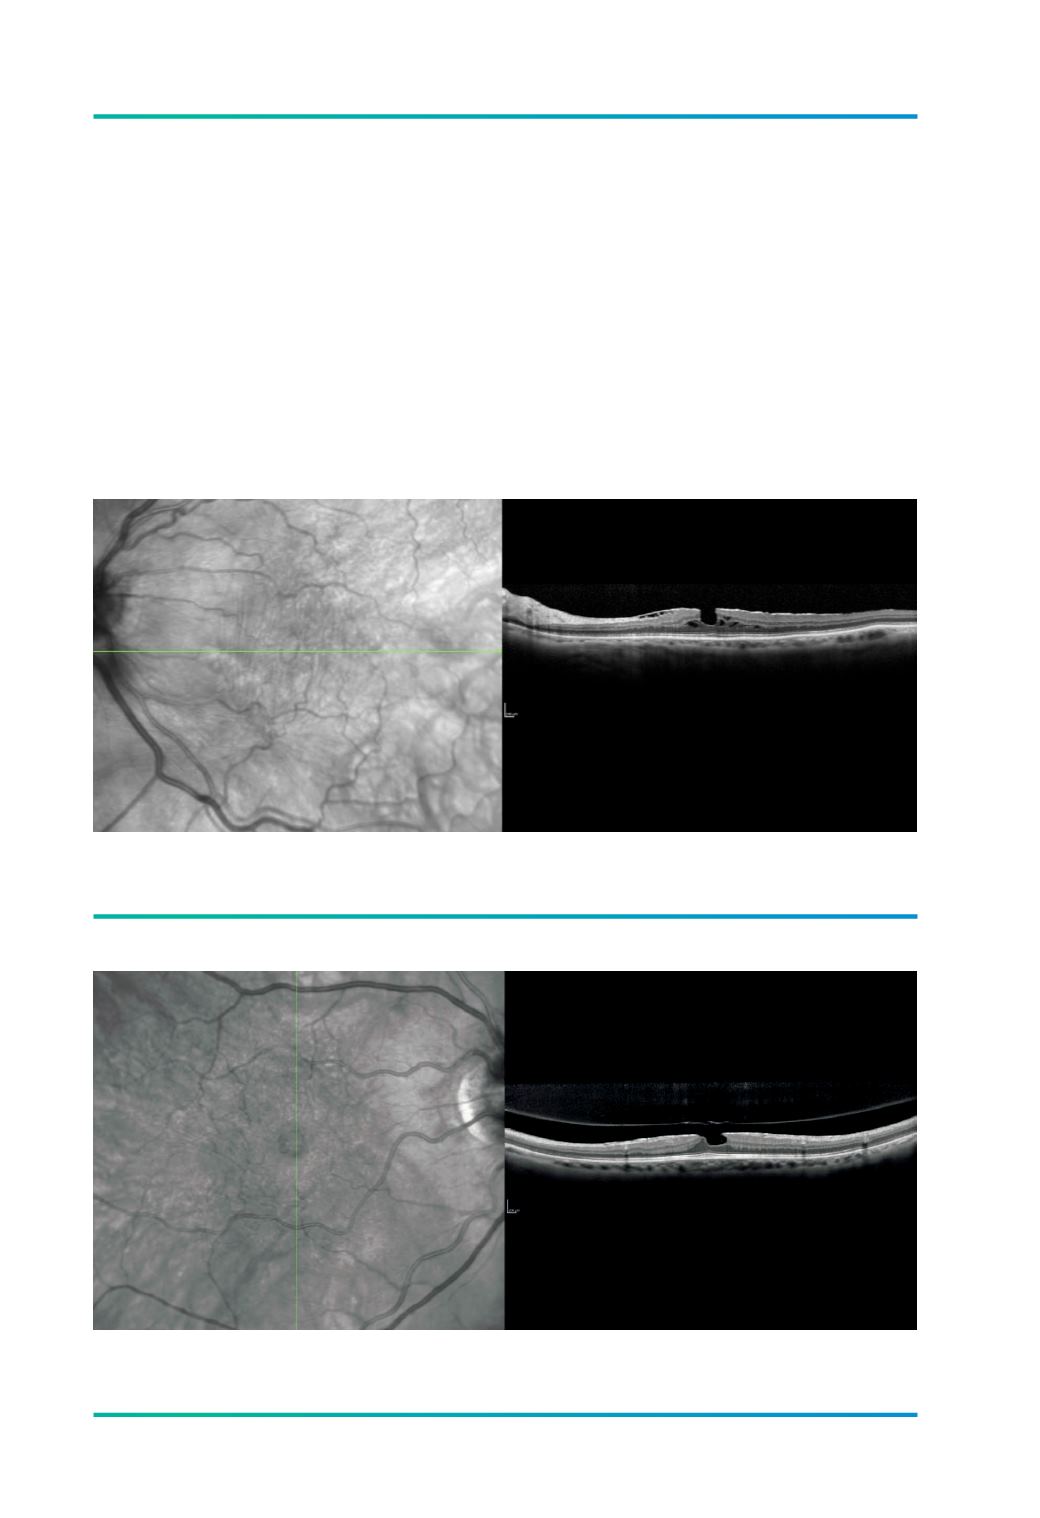

Figura 3.

Membrana epirretiniana com buraco lamelar.

Figura 2.

Membrana epirretiniana com pseudoburaco macular.